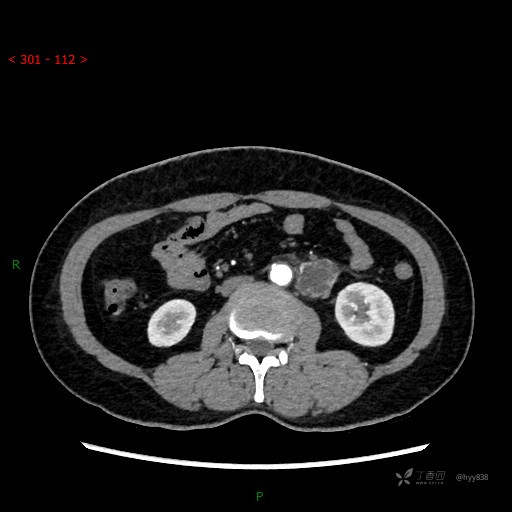

静脉期